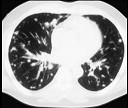

- 单项选择题.女,72岁, 咳嗽,胸闷, 呼吸困难1月余,1年前行结肠癌根治术, CT检查如图,请选择最可能的诊断 ( )

B、肺转移瘤